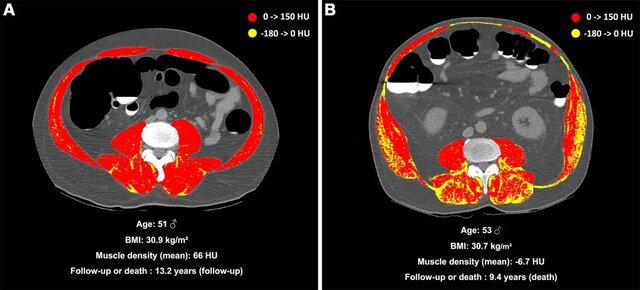

بازتاب کاملتری از ترکیب بدن را میتوان با سیتیاسکن یا امآرآی شکمی به دست آورد که میتواند انواع مختلف تجمع چربی را نشان دهد. جامعه پزشکی در درجه اول بر چربی احشایی، یعنی چربی تجمع یافته در اطراف اندامهای شکمی و استئاتوز کبد، حفظ غیرعادی چربیها در درون یاختههای کبد تمرکز میکند.

شکل دیگری از تجمع چربی میوستئاتوز است و زمانی رخ میدهد که چربی در عضلات انباشته شود. از آنجایی که میوستئاتوز اغلب در بیمارانی دیده میشود که پیش از این بیمار بود i و برای بیماری دیگری تحت تصویربرداری پزشکی قرار گرفتهاند، اطلاعات کمی در مورد خطرات سلامتی آن در بیماران بدون علامت وجود دارد.

به همین دلیل دکتر ناچیت و همکارانش دنبال شناسایی ارتباط بین میوستئاتوز و خطر مرگومیر بودند؛ در حالی که همزمان چربی احشایی، استئاتوز کبد، میوپنی (تضعیف عضلات) و چاقی را مورد بررسی قرار دادند.

از ۸۹۸۲ بزرگسالی که در این تحقیق شرکت کردند، در مجموع ۵۰۷ نفر حین دوره پیگیری فوت کردند. میوستئاتوز با افزایش خطر عوارض جانبی عمده همراه بود و در ۵۵ درصد از شرکتکنندگان فوتشده در تحقیق مشاهده شد. خطر مرگ مطلق در ۱۰ سال در افراد مبتلا به میوستئاتوز ۱۵.۵ درصد بود که در مقایسه با چاقی ۷.۶ درصد، استئاتوز کبد ۸.۵ درصد یا میوپنی ۹.۷درصد قرار دارد.